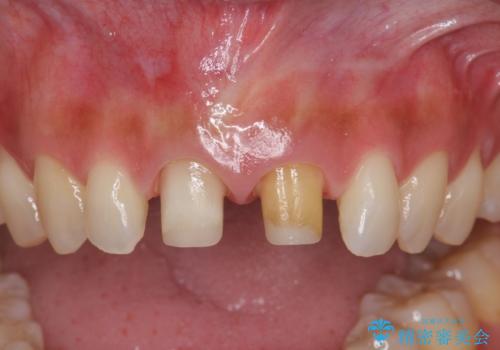

- 3週間後に迫った結婚式までになんとか前歯をきれいにしたいという希望で来院されました。

一回の治療時間を長く取り、限られた時間で最大限の結果を出せるよう集中治療を計画します。

ただ見えるクラウンを白くきれいにするのではなく、長期的な歯の予後を考えると根管治療・ファイバーコア築盛・精密な歯牙形成等クリアすべき条件は多々あると言えます。